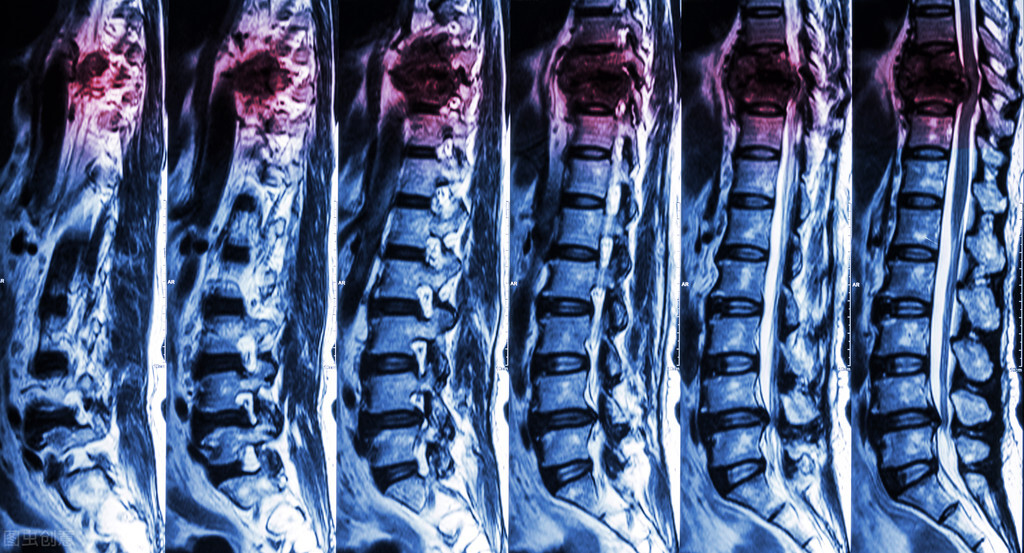

这类患者的分类是“脊髓型颈椎病”,其所占比例(颈椎病家族中)只有10%左右,发生可能性较小,但其致残率极高,因为即使及时进行治疗,避免了瘫痪的后果,也可能因为治疗时间的不同,残留一些异常。

我们对于颈椎病的认知:“优先保守,只有保守无效时才需要手术”,但对于已经确诊脊髓型颈椎病的患者而言,“保守”这两个字想都不要想,根本不需要犹豫,医生只会建议你手术,而且还是争分夺秒的手术,你的未来人生完全取决于你犹豫考虑的时间,治疗的越早远期效果也就越好,反之则是负面的变化。

1,脊髓型颈椎病患者往往存在腿脚发软、走路无法保持直线,有脚踩棉花之感。

2,患者的上肢(手臂)也会有一些变化,比如感觉手不听使唤,无力等症状(筷子拿不住掉落,手部无法用力,系鞋带变得困难等)。

3,部分患者还可能在排泄方面存在异常,比如尿频、尿急、尿不尽、大便干结、排泄困难等。